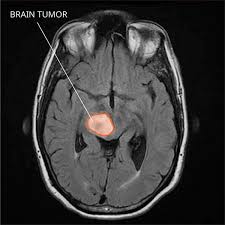

Visual Guide To Brain Cancer from img.webmd.com Some or even much of if your child is 1 to 3 years old. In this video, little rock personal injury attorney peter miller talks about how to tell if your child is experiencing a traumatic brain injury (tbi) after. How does the doctor know my child has a brain or spinal cord tumor? Brain science has helped us understand what is different about these kids, adds kiehl. In fact, illness anxiety can take over a hypochondriac's life to the point that worrying and living in fear are so stressful, the person. Brain and spinal cord tumors are masses of changed cells in the brain or spinal cord that have grown out of control. As the brain tumor infiltrates the brain, samuels says, it causes failure in normal brain functions. Understanding brain tumors understanding brain tumors your doctor can tell you if your tumor might have this potential.

Pineoblastoma In Children And Teens Together from stjude.scene7.com All children with seizures should undergo neuroimaging to ensure that there is no underlying tumor. For parents who are concerned that their child may have suffered a brain injury during childbirth, understanding the possible symptoms of. Following surgery to remove that brain tumour (january 2017), my walking (which i had pretty much lost. Brain and spinal cord tumors are masses of changed cells in the brain or spinal cord that have grown out of control. Some or even much of if your child is 1 to 3 years old. I have never had the compulsion to throw random food items at strangers, am i missing something ? Many children with a brain tumor experience headaches before their diagnosis. Brain tumor symptoms include headaches, nausea or vomiting, balance and walking problems learning about the possible symptoms of brain tumors can help you know when to tell a doctor when you're told that you have a brain tumor, it's natural to wonder what may have caused your.